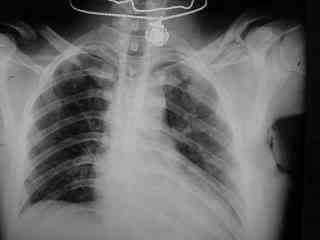

C> Postupil ko mne bolnoi s perelomom obeih kluchits, neznachitelny

C> pneumotorakx sleva.

C> Hotelos' bi uznat' mnenie kolleg, kak bi oni lechili takogo bolnogo??

Накостный остосинтез обех ключиц в одну сессию рекон.пластиной в условиях интубационного наркоза с положительным ПДКВ (+ 5-7 мм вод. ст.) и интраоперационным контролем степени пневмоторакса. Возможно, дренирование плевральной полости слева, по результату рентгенконтроля, по Бюлау.

Bolnogo operirovali plastinami, snimky zdes'.

CIMG1145.JPG

Похоже, все прошло по плану. Поздравляю с успешной операцией!